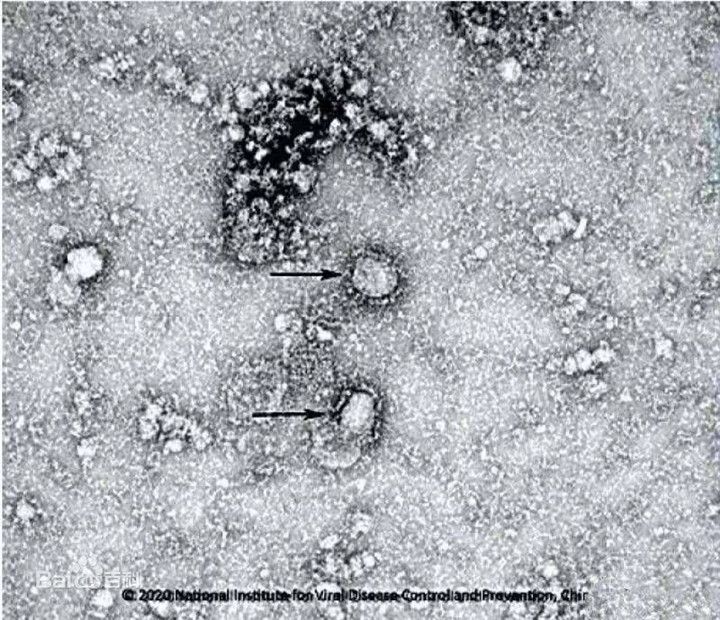

新型冠狀病毒形態(tài)